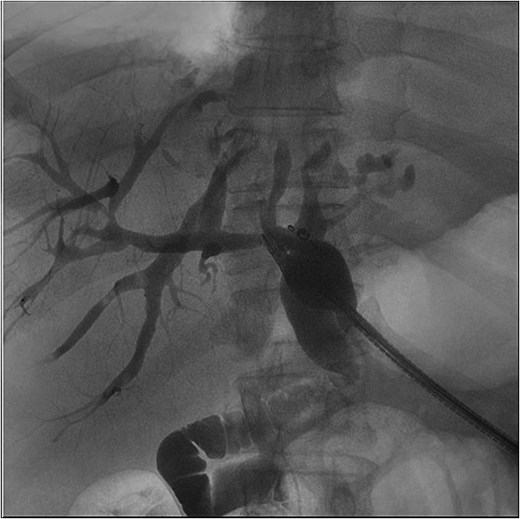

The patient presented the following day with fevers and new chest pain. He underwent a computed tomography angiography (CTA) chest and abdomen/pelvis, which revealed a left lower lobe consolidation and a moderate pericardial effusion. His hepatic abscess had increased in size to 7.2 × 5.5 cm (Fig. 2). Cardiology was consulted, and a bedside echo was performed, which found acute pericarditis. He was admitted and started on IV antibiotics and colchicine for his pericarditis. GI subsequently performed an ERCP, which showed no biliary or anastomotic stricture (Fig. 3). It was thought that it was likely a choledochal cyst, and the plan was for elective left hepatectomy. He was transitioned to oral antibiotics and discharged with colchicine for 3 months.

Fluoroscopic image from ERCP—a representative image from the patient’s ERC. This demonstrates biliary ductal dilation but no signs of obstructing stones or stricture. Additionally, this image illustrates the cystic cavity does not communicate with the biliary system.